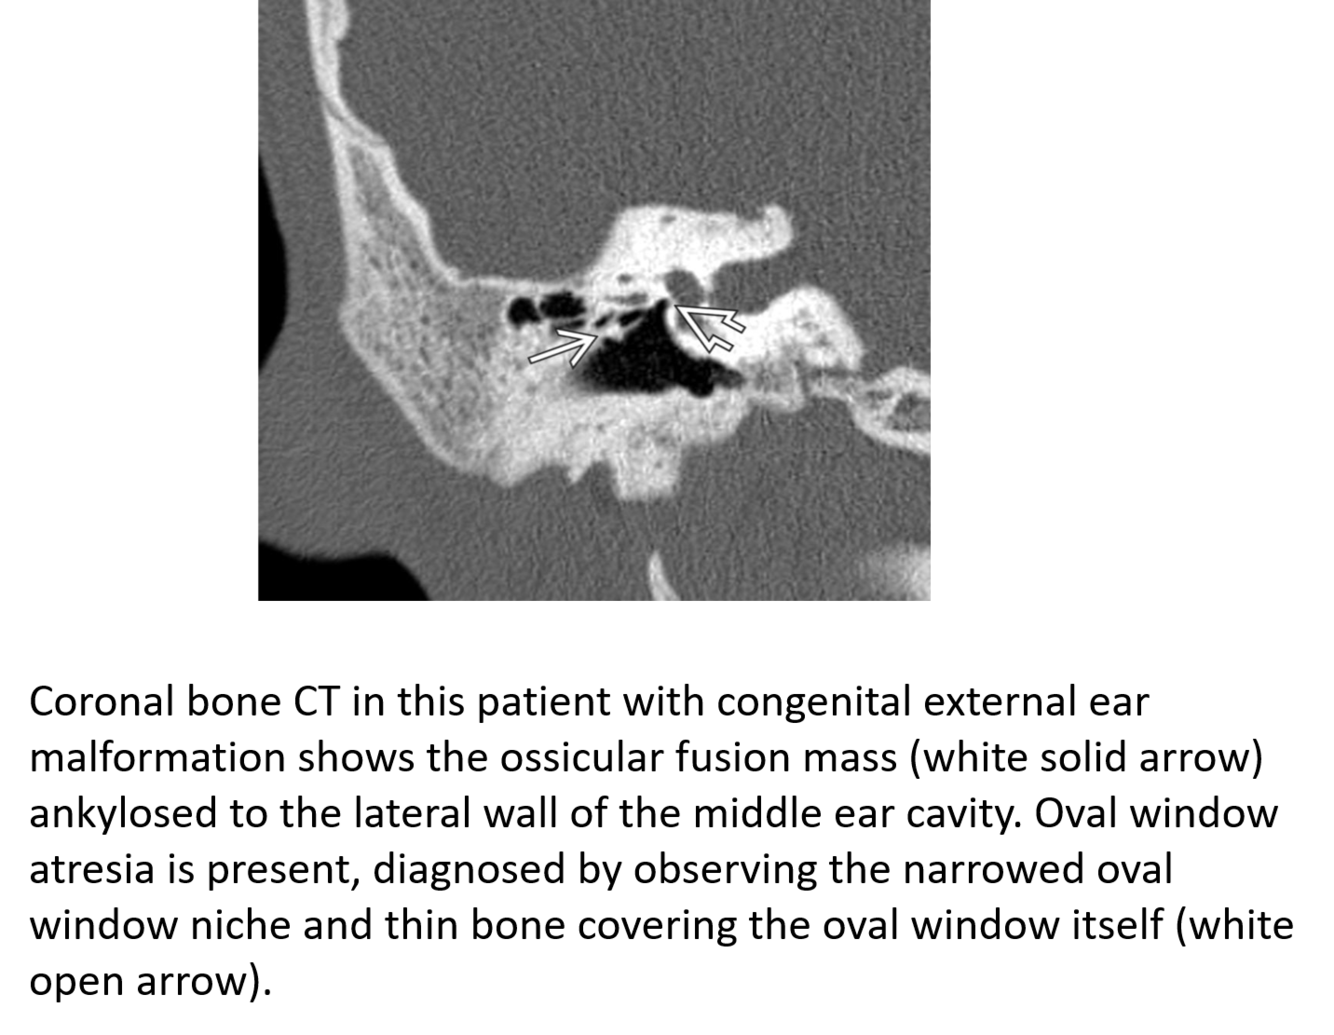

Congenital External and Middle Ear Malformation

Medial epitympanic congenital cholesteatoma that erodes portions of the ossicles.

Solid arrow: choleastatoma

open arrow: erosion of the long process of the incus and hub of the stapes

Curved arrow: erosion of the lateral bony margin of the tympanic segment of the facial nerve canal

**Tympanic segment of the facial nerve will always be aberrant in the location of the oval window instead of inferior to the lateral semi-circular canal